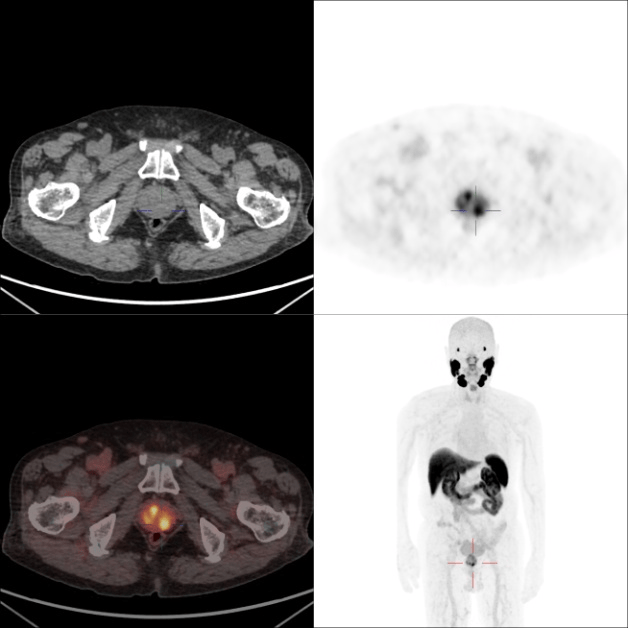

病例一

患者,男,89岁,总前列腺特异性抗原:8.31ug/L ↑

前列腺外形略饱满伴PSMA摄取增高灶,符合前列腺癌影像表现;另检出右肾可疑占位